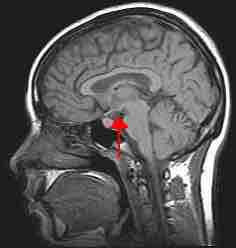

Limbic system, brain stem, and spinal cord

An image of the brain showing the limbic system in relation to the brain stem and spinal cord.

Hypothalamus

An image of the brain showing the location of the hypothalamus.